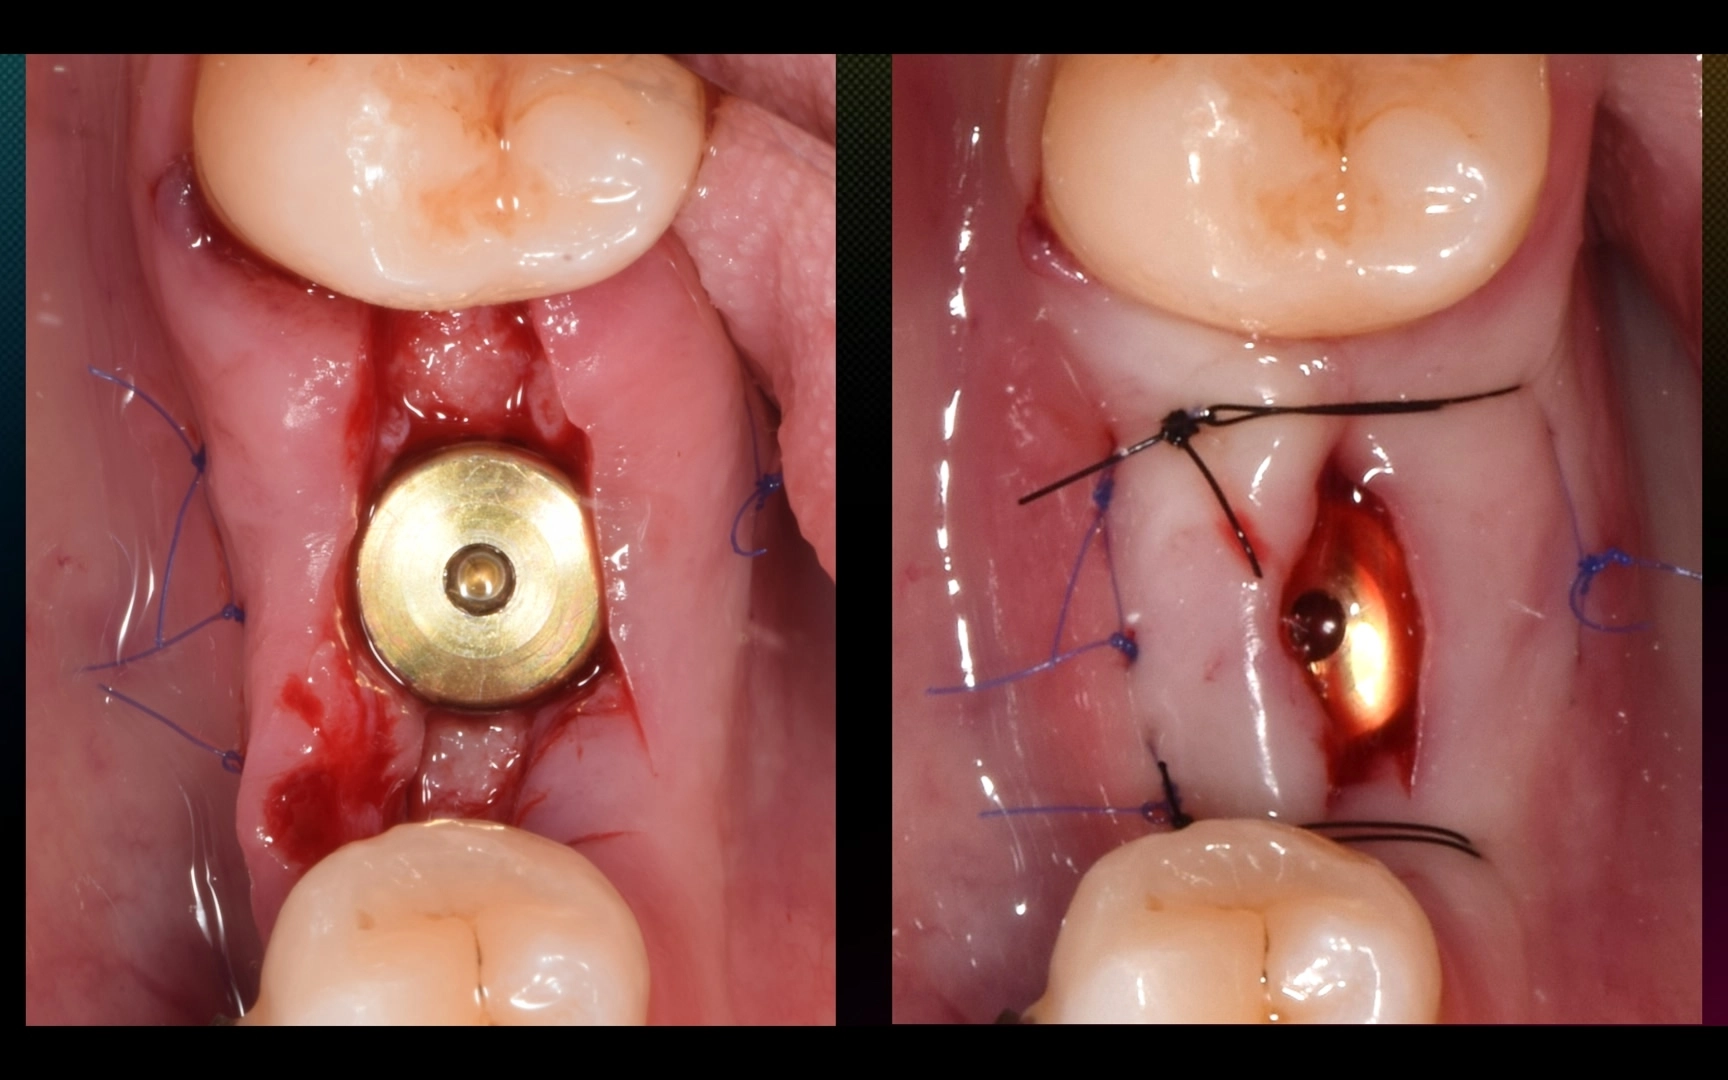

1. Имплантация MIS C1 в области 4.6 зуба, ФДМ, пластика десны с обеих сторон альвеолярного гребня (СТТ из бугра).

2. Через 5 месяцев после имплантации (пациентка раньше не смогла, обычно на н/ч выжидаем 3 месяца) — установка коронки с помощью ортопедического расщепления мягких тканей.

P/S Ждём полного созревания мягких тканей.